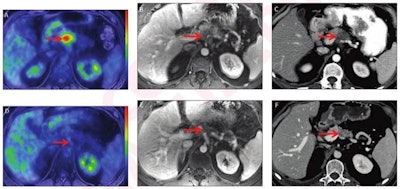

52-year-old man with locally advanced pancreatic adenocarcinoma and major pathologic response. Pretreatment (A-C) and post-treatment (D-F) images after eight cycles of systemic Folfirinox and consolidative chemoradiation. Baseline CA 19-9 was 145 U/ml. Pretreatment whole-body axial fused PET/MRI showed FDG-avid lesion in body of pancreas (arrow, A) with SUVmax 7.1 and SUVgluc 8.0. Lesion was hypoenhancing on axial contrast-enhanced T1-weighted MR image (arrow, B) from focused abdominal PET/MRI and on CT (arrow, C). Pretreatment CT tumor volume was 10.3 cm3. Post-treatment whole-body axial fused PET/MRI showed complete metabolic response (arrow D) with SUVmax 1.9 and SUVgluc 1.9. Lesion was indistinct on axial contrast-enhanced T1-weighted MRI (arrow, E) and CT (arrow, F), and there was upstream pancreatic parenchymal atrophy. Post-treatment CT tumor volume was 0.46 cm3. There was normalization of CA 19-9. Relative change in SUVmax was -73%, and relative change in SUVgluc was -76%. Based on change in tumor size, response was categorized as partial response per RECIST. Relative change in tumor volume was -96%. Pathology showed major pathologic response (College of American Pathologists score 1). Images and caption courtesy of the American Roentgen Ray Society and the American Journal of Roentgenology.

52-year-old man with locally advanced pancreatic adenocarcinoma and major pathologic response. Pretreatment (A-C) and post-treatment (D-F) images after eight cycles of systemic Folfirinox and consolidative chemoradiation. Baseline CA 19-9 was 145 U/ml. Pretreatment whole-body axial fused PET/MRI showed FDG-avid lesion in body of pancreas (arrow, A) with SUVmax 7.1 and SUVgluc 8.0. Lesion was hypoenhancing on axial contrast-enhanced T1-weighted MR image (arrow, B) from focused abdominal PET/MRI and on CT (arrow, C). Pretreatment CT tumor volume was 10.3 cm3. Post-treatment whole-body axial fused PET/MRI showed complete metabolic response (arrow D) with SUVmax 1.9 and SUVgluc 1.9. Lesion was indistinct on axial contrast-enhanced T1-weighted MRI (arrow, E) and CT (arrow, F), and there was upstream pancreatic parenchymal atrophy. Post-treatment CT tumor volume was 0.46 cm3. There was normalization of CA 19-9. Relative change in SUVmax was -73%, and relative change in SUVgluc was -76%. Based on change in tumor size, response was categorized as partial response per RECIST. Relative change in tumor volume was -96%. Pathology showed major pathologic response (College of American Pathologists score 1). Images and caption courtesy of the American Roentgen Ray Society and the American Journal of Roentgenology.Panda and colleagues found that pre- and post-treatment changes in tumor metrics on PET/MRI and CT were associated with pathologic response.